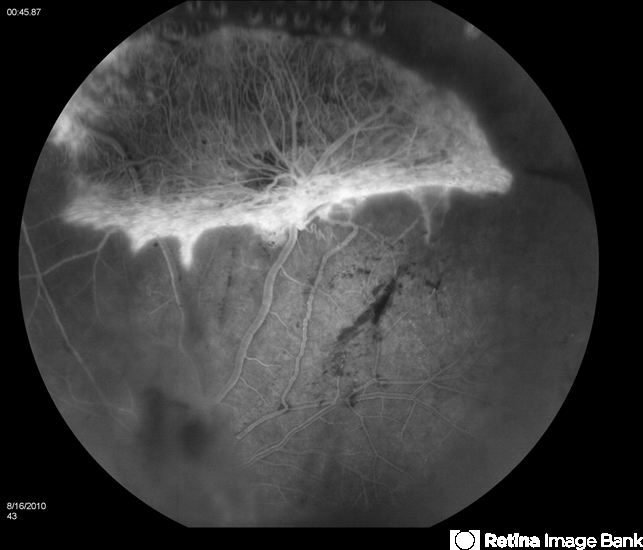

- Susac's syndrome

- Bill McVerry, Carolina Eye Associates

- Recurrent proliferative disease after initial stabilization with PRP.